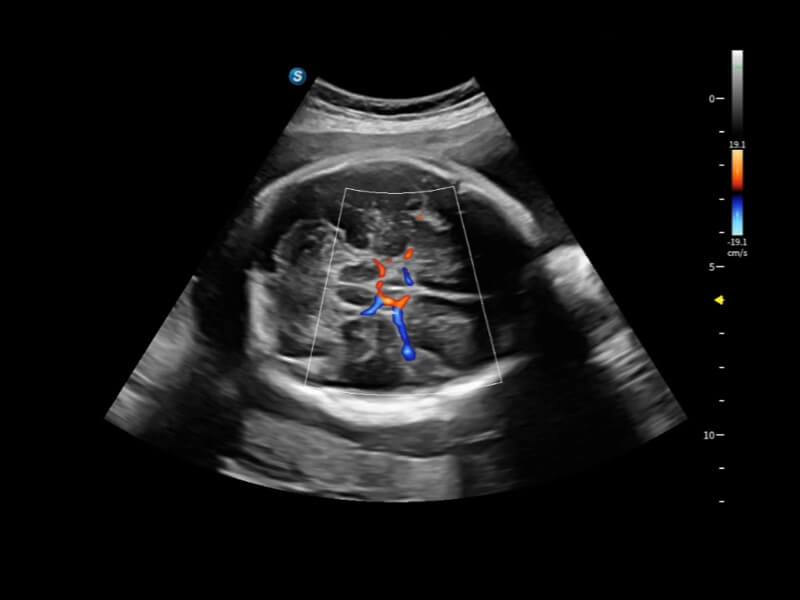

Fine-tuned Hemodynamic Solution

A wide variety of hemodynamic diagnostic techniques enable effective blood flow signal detection across different scenarios.

• FHR

FHR enables the observation of microvascular structure within organs with enhanced sensitivity and improved resolution, ensuring the precision in representing the actual state of blood circulation.

• Bright Flow

Bright Flow offers 3D-like color Doppler flow visualization without requiring a volume transducer, thereby strengthening the boundary definition of vessel walls.

• Micro F

Micro F efficiently distinguishes subtle blood flow signals from overlaying tissue motion, enabling heightened sensitivity and spatial resolution in hemodynamic depiction.